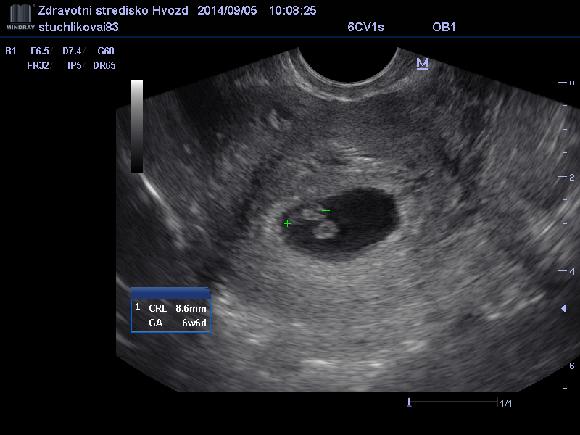

@pulpk ahojky,tak dneska kontrolní utz a miminko odpovídá 6+6tt,což podle ms vůbec nesedí,moje poslední ms byla 29.6...takže já skutečně otěhotněla prostě až nějak až po termínu ms.

Srdíčko bije,jsme moc štastní.

@lentilkalentilka asi bych šla k dr,na krev,to je jistota úplná.Já teda byla na krvi 9 dní po vynechání a testy negativní,potom píchnutá vyvolávačka a až téměř tři týdny po termínu MS,konečně z krve pozitivní testy,50...dva dny na to 220...a dneska jsem v 6+6tt dle velikosti miminka a vše je ok,zkrátka jsem otěhotněla mnohem dýl🙂